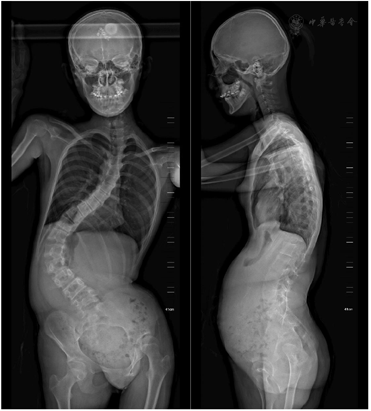

辅助检查:生化全套示碱性磷酸酶为201.8 U/L(参考范围47~185 U/L),总蛋白为60.6 g/L(参考范围65~85 g/L),白蛋白为39.1 g/L(参考范围40~55 g/L),尿素为2.8 mmol/L(参考范围2.9~7.5 mmol/L),肌酐为26 µmol/L(参考范围44~106 µmol/L),总二氧化碳19.9 mmol/L(参考范围22~32 mmol/L),L-胆固醇1.84 mmol/L(参考范围1.89~3.10 mmol/L),载脂蛋白A I为0.85 g/L(参考范围1.00~2.05 g/L),载脂蛋白B为0.56 g/L(参考范围0.6~1.2 g/L)其余正常;肌酸激酶MB同工酶为20 U/L(参考范围1~18 U/L);凝血五项示活化部分凝血活酶时间为35.6 s(参考范围25.0~31.3 s),其余正常。全脊柱普放X线摄影(图1)示脊柱呈明显"S"型弯曲,以胸椎为中心,两侧肋骨12对,未见明显骨性异常,肋间肌尚可,脊柱椎体形态大致正常,未见明显椎体骨性异常,各椎体间隙未见明显异常改变,脊柱侧凸畸形(Cobb角96°,SVA 2.9 cm,冠状面平衡偏离4.8 cm)。立位全下肢X线摄影(图2)示双下肢不等长,骨盆左倾(骨盆倾斜角20°)。